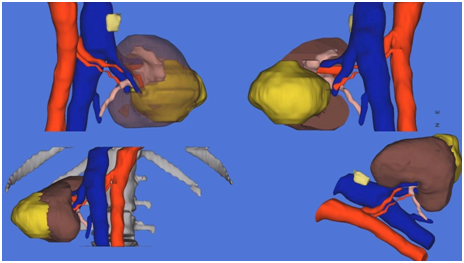

「東文教授非常重視術前規劃,此次他在深圳首次使用了原創專利技術——腹腔鏡腎臟手術個體化腎血管評價系統(SIREN 系統),通過手術前對患者的腎臟血管情況進行三維立體重建,不僅清晰顯示出了患者腎臟的動脈、靜脈血液供應情況,還可以預先對手術切除層面進行演示。」泌尿外科主任田軍教授說,藉助這項技術可對腎臟血管進行直觀、量化的評估,可以實現術前精細化的規劃,為複雜腎癌手術提供安全保障。